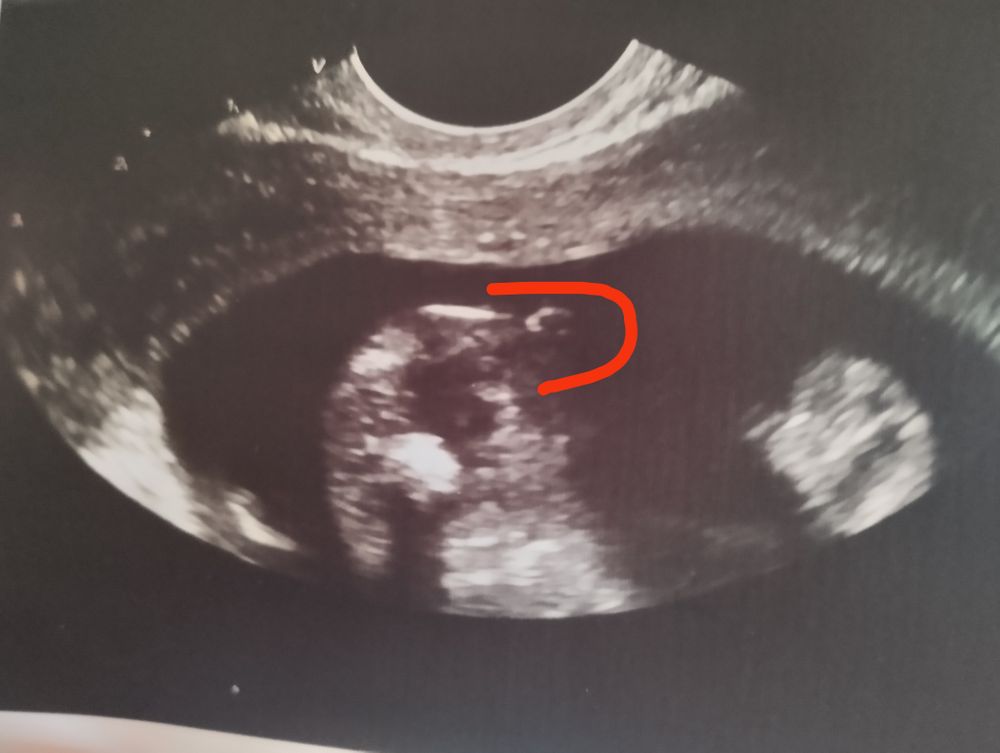

Пол ребёнка

Изменения и болезни во время БСегодня была на узи. 15 недель и 2 дня. Все показатели в норме. Попросила посмотреть, кого мы ждём. Долгожданный мальчик😍 Я сразу не поверила, что у меня под сердцем мужичок, прослезилась от счастья🥰Спросила у узиста, точно, пол не изменится? Она крупным планом показала «доказательства»😂 В первые две беременности дочками я так не волновалась перед узи, как сегодня.